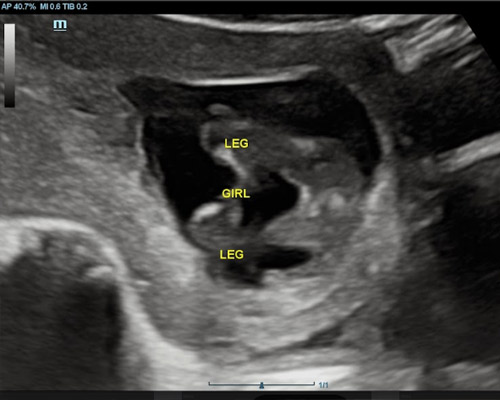

A gender scan is a specialised ultrasound that focuses on identifying your baby’s gender with a high level of accuracy.Using modern imaging equipment, the sonographer carefully looks at your baby’s position and development to determine gender, usually available from 15 weeks onwards. During the scan, you’ll be guided through what can be seen on the screen so you feel fully informed.

- 2D ultrasound to determine your baby’s gender